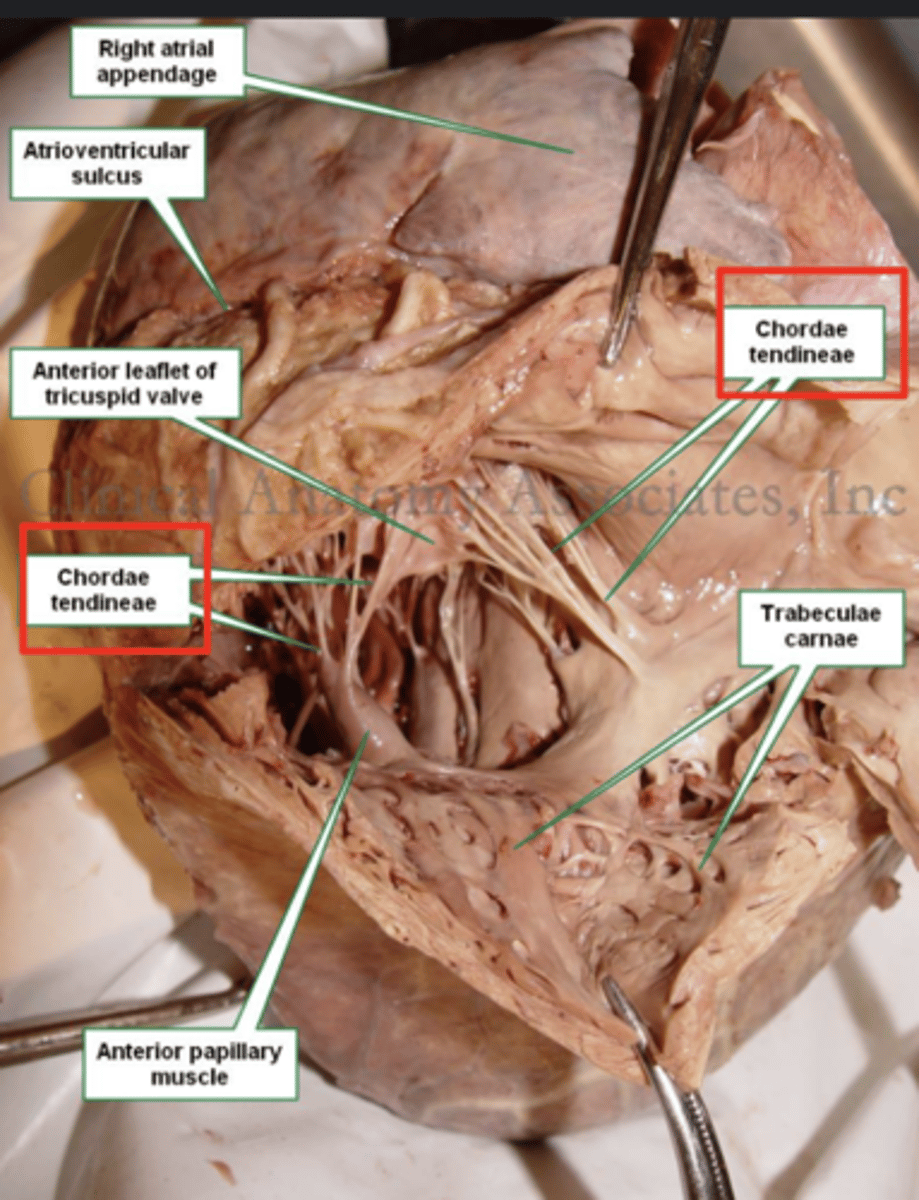

Describe the two portions of the medial/septal face/wall of the right ventricle.

infundibulum or outflow region or conus arteriosus (smooth and membranous)

trabeculae carnae (muscular and irregular)

What connect the cusps of the valve a to papillary muscles in the

right ventricle?

Chordae tendinae

With the contraction of the walls of the ventricle what's the action of the papillary muscles?

contract as well

With the contraction of papillary muscles what will be happen with the valve?

Close

What role do the papillary muscles and chordae tendineae play in the function of the tricuspid valve?

During ventricular systole (contraction), the tricuspid valve closes

The papillary muscles contract at the same time as the ventricle.

This contraction tightens the chordae tendineae, pulling the valve leaflets taut and holding them in place.

This mechanism prevents the valve leaflets from prolapsing (bulging back) into the atrium under the high pressure of ventricular contraction.

What role does the moderator band play in the conduction system?

Allows the wave to reach the papillary muscles, inducing their contraction simultaneously with that of the ventricles.

REMEMBER: PAPILLARY MUSCLES ACT THROUGH THE CHORDAE TENDINAE TO CONTROL THE TRICUSPID AND MITRAL VALVES.